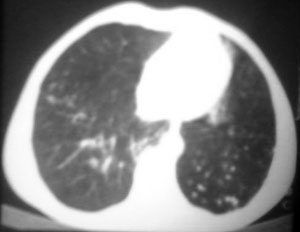

以下是引用逸风在2006-9-12 14:57:00的发言:[br]ct显示双肺上叶点片状及纤维索条状密度不均影,肺野外带近胸膜可见大小不等的含气空腔,壁略厚,境界清晰,未见液平面,中下肺野散在小片状及点状高密度影;纵隔内显示点状钙化,未见明显淋巴结肿大,构成胸廓诸骨未见明显异常.[br]诊断意见:1.双肺结核合并支气管播散;2.双肺上肺大泡.